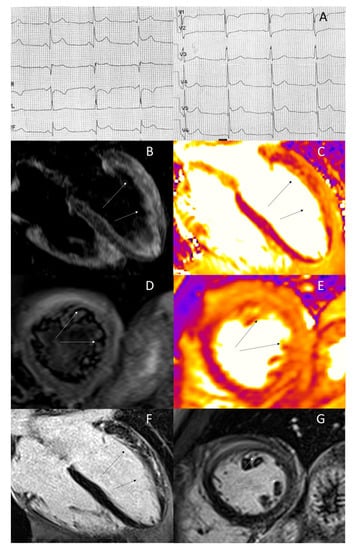

- De Lazzari, M.; Zorzi, A.; Baritussio, A.; Siciliano, M.; Migliore, F.; Susana, A.; Giorgi, B.; Lacognata, C.; Iliceto, S.; Perazzolo Marra, M.; et al. Relationship between T-wave inversion and transmural myocardial edema as evidenced by cardiac magnetic resonance in patients with clinically suspected acute myocarditis: Clinical and prognostic implications. J. Electrocardiol. 2016, 49, 587–595. [Google Scholar] [CrossRef] [PubMed]

- Perazzolo Marra, M.; Zorzi, A.; Corbetti, F.; De Lazzari, M.; Migliore, F.; Tona, F.; Tarantini, G.; Iliceto, S.; Corrado, D. Apicobasal gradient of left ventricular myocardial edema underlies transient T-wave inversion and QT interval prolongation (Wellens’ ECG pattern) in Tako-Tsubo cardiomyopathy. Heart Rhythm 2013, 10, 70–77. [Google Scholar] [CrossRef]

- Migliore, F.; Zorzi, A.; Marra, M.P.; Basso, C.; Corbetti, F.; De Lazzari, M.; Tarantini, G.; Buja, P.; Lacognata, C.; Thiene, G.; et al. Myocardial edema underlies dynamic T-wave inversion (Wellens’ ECG pattern) in patients with reversible left ventricular dysfunction. Heart Rhythm 2011, 8, 1629–1634. [Google Scholar] [CrossRef]

- Zorzi, A.; Perazzolo Marra, M.; Migliore, F.; De Lazzari, M.; Tarantini, G.; Iliceto, S.; Corrado, D. Relationship between repolarization abnormalities and myocardial edema in atypical Tako-Tsubo syndrome. J. Electrocardiol. 2013, 46, 348–351. [Google Scholar] [CrossRef]

- Migliore, F.; Zorzi, A.; Perazzolo Marra, M.; Iliceto, S.; Corrado, D. Myocardial edema as a substrate of electrocardiographic abnormalities and life-threatening arrhythmias in reversible ventricular dysfunction of takotsubo cardiomyopathy: Imaging evidence, presumed mechanisms, and implications for therapy. Heart Rhythm 2015, 12, 1867–1877. [Google Scholar] [CrossRef] [PubMed]